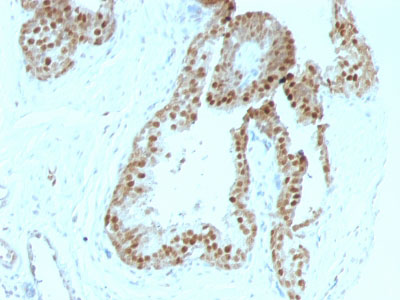

Formalin-fixed, paraffin-embedded human Colon Carcinoma stained with p57 Monoclonal Antibody (KIP2/880).

Formalin-fixed, paraffin-embedded human Prostate Carcinoma stained with p57 Monoclonal Antibody (KIP2/880). |

Recognizes a protein of 57kDa, identified as p57Kip2. It shows no cross-reaction with p27Kip1. p57Kip2 is a potent tight-binding inhibitor of several G1 cyclin complexes, and is a negative regulator of cell proliferation. Anti-p57 has been used as an aide in identification of complete hydatidiform mole (CHM) (no nuclear labeling of cytotrophoblasts and stromal cells) from partial hydatidiform mole (PHM) in which both cytotrophoblasts and stromal cells stain. The histological differentiation of complete mole, partial mole, and hydropic spontaneous abortion is problematic. Most complete hydatidiform moles are diploid, whereas most partial moles are triploid. Ploidy studies will identify partial moles, but will not differentiate complete moles from non-molar gestations. Complete moles carry a high risk of persistent disease and choriocarcinoma, while partial moles have a very low risk. In normal placenta, many cytotrophoblast nuclei and stromal cells are labeled with this antibody. Similar findings apply to PHM and hydropic abortus tissues. Intervillous trophoblastic islands (IVTIs) demonstrate nuclear labeling in all three entities and serve as an internal control.